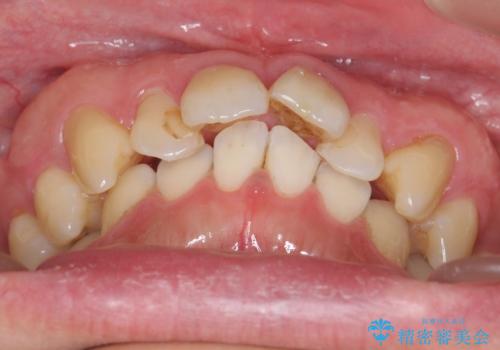

- 前歯の突出を主訴に来院。

全体矯正を行うとなると健康な歯を4本抜歯することになるため、歯は抜かず上だけの部分矯正で最小限で前歯を整えることにしました。

前歯は少し細く削って前に出ないように整えました。

左上の1番目の前歯は神経を取ってある歯でした。今後変色もすすんでいくため、治療のやり直しを行いセラミックでかぶせました。

左上の2番目の前歯は虫歯治療を行い、神経治療まで行っています。